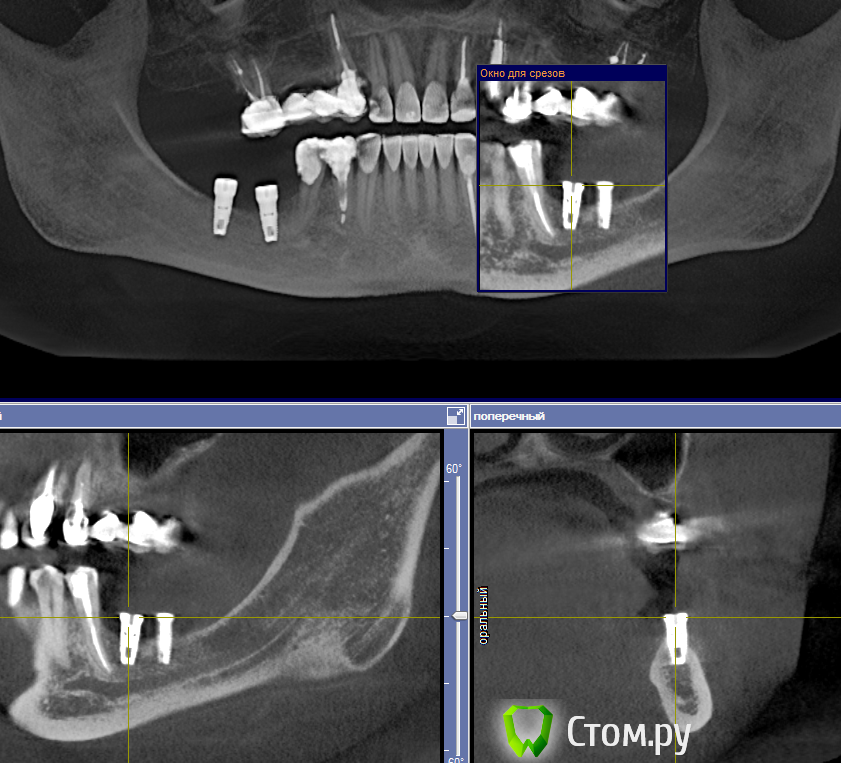

Libero15 Опубликовано 16 февраля, 2014 Поделиться Опубликовано 16 февраля, 2014 Подскажите, знающие люди, что за система??Заранее спасибо! Ссылка на комментарий

red_butler Опубликовано 16 февраля, 2014 Поделиться Опубликовано 16 февраля, 2014 2 red_butler: "А 3.7 Вас не смущает?"Я просто осторожен в своих выссказываниях, срезы на 3.7 не информативны. Система имплантов не знакома Ссылка на комментарий

doca Опубликовано 16 февраля, 2014 Поделиться Опубликовано 16 февраля, 2014 Подскажите, знающие люди, что за система??Заранее спасибо!по глубокой шахте похож на нобель риплэйс Ссылка на комментарий

Bier Опубликовано 17 февраля, 2014 Поделиться Опубликовано 17 февраля, 2014 По кт срезу имплант не определишь, сделайте орто или прицельный Ссылка на комментарий